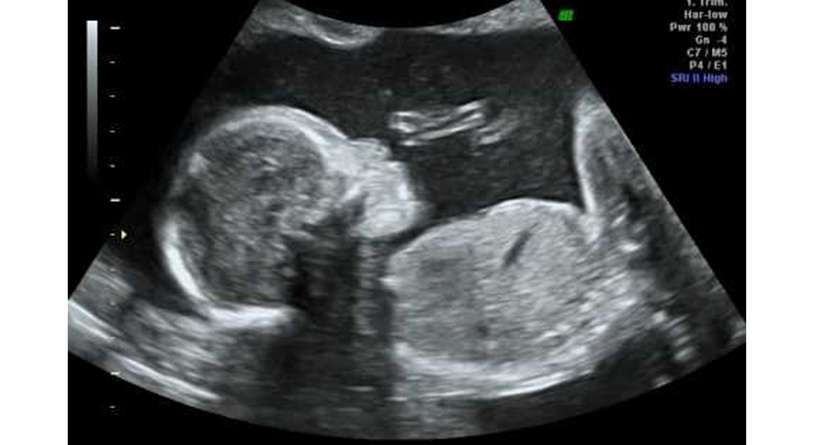

تشابه اعضاء الجنين الذكر والانثى هي من الأمور الطبيعية التي قد تحدث قبل الوصول الى الشهر الرابع من الحمل، تعرفي على اسباب هذا التشابه وكيفية التمييز بين الجنسين.

متى يمكن معرفة جنس الجنين

على الرغم من أن الجهاز التناسلي للذكر وللأنثى يبدأن في التكون من الأسبوع السادس من الحمل، إلا أن الذكر والأنثى يبدوان متشابهين كثيراً في التصوير بالموجات فوق الصوتية حتى حوالي الأسبوع الـ14 ويكون من الصعب التمييز بينهما لعدة أسابيع. ومع الوصول الى الأسبوع الـ18، يصبح بإمكانك اكتشاف جنس الجنين وذلك في حال كان الجنين متخذ للوضعية المناسبة التي تسمح للطبيب برؤية أعضائه.

من المعروف ان الشهر الرابع من الحمل هو المسؤول عن الكشف عن جنس الجنين، فقبل هذا الشهر، تتكون الأعضاء التناسلية له ولكن لا يمكن اكتشافها إلا للوصول للشهر الرابع، ومن الجدير بالذكر، ان من الممكن ان تتشابه الأعضاء التناسلية في هذا الشهر وذلك بسبب إخطاء الطبيب في التمييز بين العضو الذكري والحبل السري، فقد يظن الطبيب ان الحبل السري هو قضيب الجنين أي عضوه الذكري. وفي هذا السياق، يمكن ان يأخذ الجنين وضعية لا تسمح للطبيب برؤية أعضائه، ومن هنا ننصحك بالانتظار للشهر الخامس للتأكد بشكل دقيق وصحيح ومن جنس جنينك.

قبل وأثناء الشهر الرابع من الحمل، قد تتشابه أعضاء الجنين للأسباب التي ذكرناها، وتبدأ هذه الأعضاء بالاختلاف في الشهر الرابع أو الخامس، وللتمييز بين الذكر والانثى، يظهر على شاشة السونار قضيب وهو يدل على العضو الذكري، أما في حال كان الجنين أنثى، تظهر 3 خطوط بيضاء وتكون هي شفرات البظر.

هذه هي اسباب تشابه اعضاء الجنين في الشهر الرابع من الحمل، ولتتأكدي بشكل أفضل، من المفضل ان تشاهدي شكل الجنين بالذكر والأنثى بالسونار.